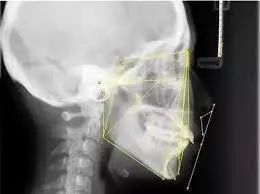

矫正前,拍摄牙齿全景片和头颅侧位X光片是必不可少的一步 | www.lovelytooth.com

接下来,我拍摄了曲面断层和投影侧位片以及全口牙齿锥形束CT,用于描绘标志点进行线角的测量,最后用3D扫描仪记录了牙齿的全貌,牙齿矫正的全面设计不仅包括表面上的牙齿排列、侧面像的协调,而且还要深入到骨骼结构、发育潜能、动静态的颌位关系。